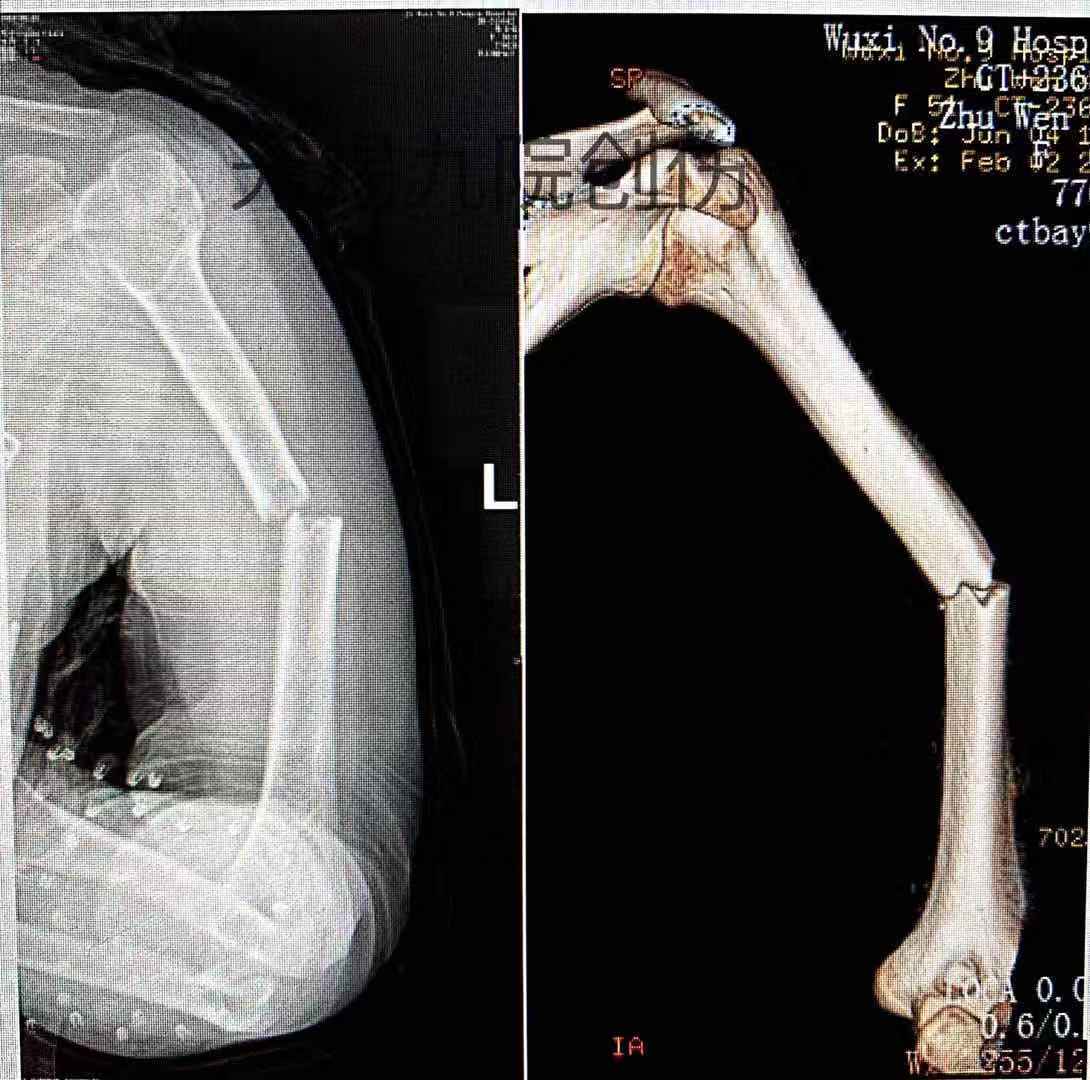

左肱骨干粉碎性骨折 - 骨科专业讨论版 -丁香园论坛

图片尺寸780x1040